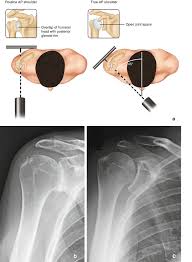

Shoulder Joint Radiology Key

Shoulder Joint Radiology Key from i2.wp.com